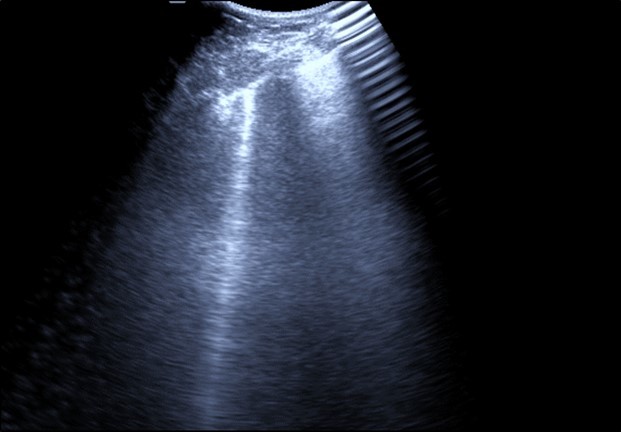

Patients with severe Covid-19 and lower respiratory tract symptoms can be initially evaluated with bed side chest ultrasound under complete protective measures.

Bed side chest ultrasound may reveal positive findings as multiple Kerley’s B lines (>3 per intercostal space), pleural wall thickening (Figure 1), patchy areas of pulmonary consolidations especially in subpleural location (Figure 2, Figure 3) and obstructive lung collapse.

Figure 1.Real time chest ultrasound showing Kerley’s B lines in patient with covid -19.

Real time chest ultrasound showing Kerley’s B lines in patient with covid -19.